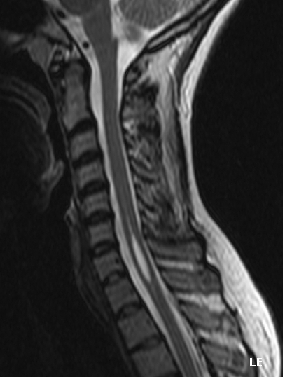

تكهف النخاع (Q3794626)

| الإنجليزية | syringomyelia |